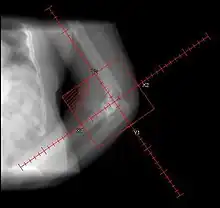

Elbow heterotopic ossification radiation therapy field, status post surgery.

Prophylactic radiation therapy for the prevention of heterotopic ossification has been employed since the 1970s. A variety of doses and techniques have been used. Generally, radiation therapy should be delivered as close as practical to the time of surgery. A dose of 7-8 Gray in a single fraction within 24–48 hours of surgery has been used successfully. Treatment volumes include the peri-articular region, and can be used for hip, knee, elbow, shoulder, jaw or in patients after spinal cord trauma.

Single dose radiation therapy is well tolerated and is cost effective, without an increase in bleeding, infection or wound healing disturbances.[6]